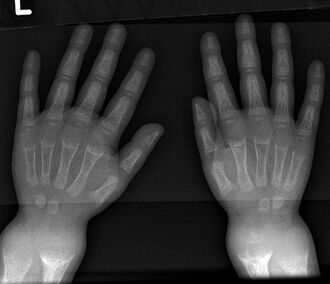

An X-ray or radiograph of an advanced patient with rickets tends to present in a classic way: the bowed legs (outward curve of long bone of the legs) and a deformed chest. Changes in the skull also occur causing a distinctive "square headed" appearance known as "caput quadratum".[14] These deformities persist into adult life if not treated. Long-term consequences include permanent curvatures or disfiguration of the long bones, and a curved back.[15]